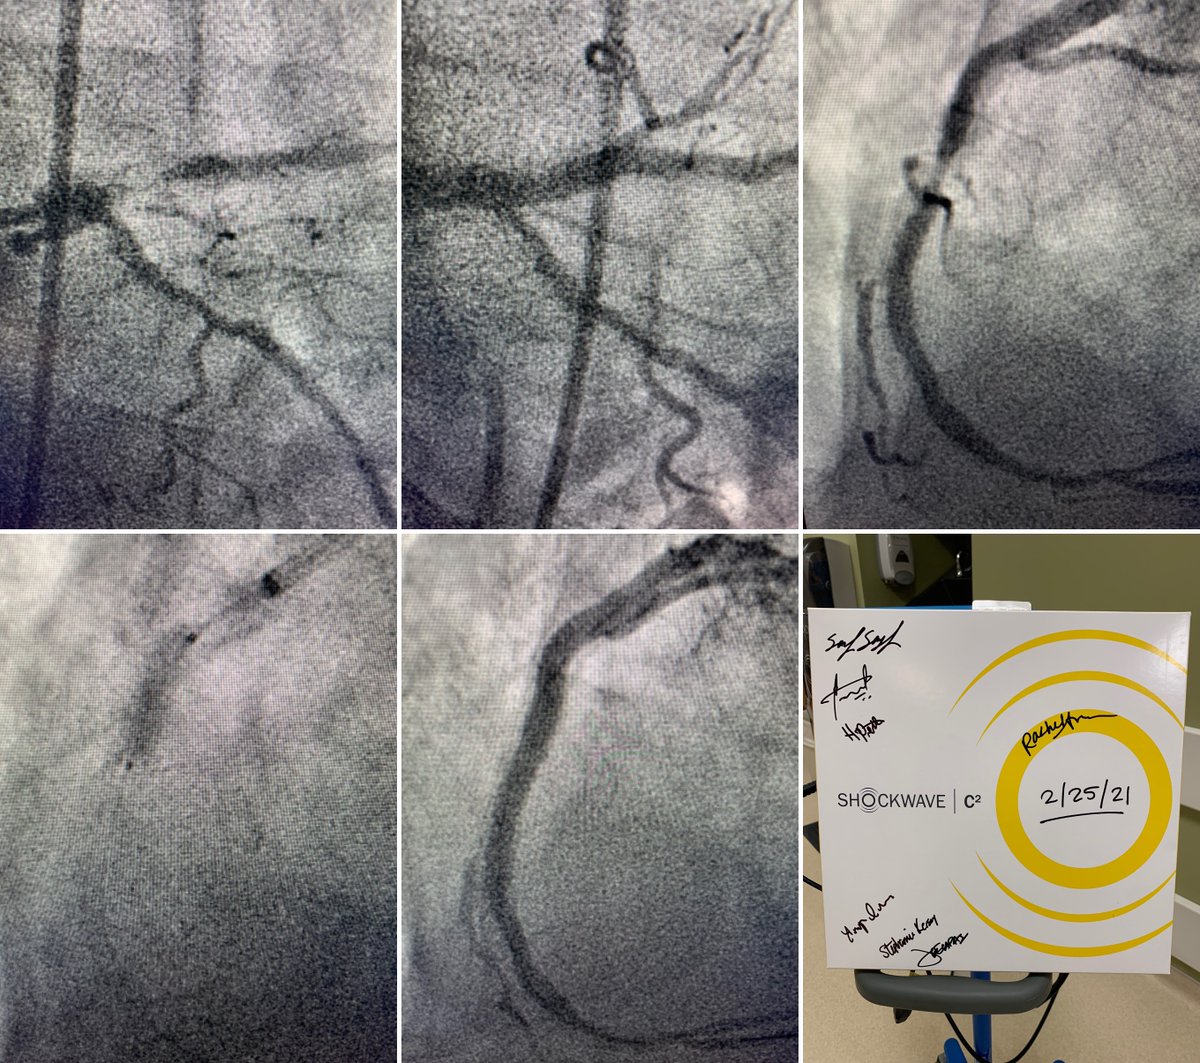

3 vessel disease, PCI of Ostia/Prox LAD, NC balloon unsuccessful. 40 pulses of 3.5x12 #ShockwaveC2, finished w/ 4.0x18 DES. RCA for 20 pulses of same C2, finished w/ 3.5x38 DES. Outstanding result by Dr. Sameh Sayfo at Baylor Scott & White Health Heart Hospital Plano! ISI bit.ly/3rnUXue